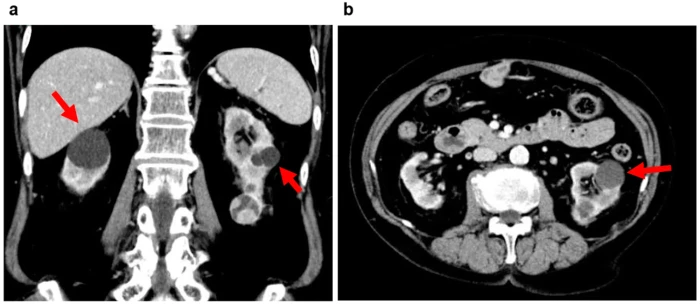

Diagnostikimi është i thjeshtë dhe shpesh i rastësishëm, pasi cistet zbulohen gjatë ekzaminimeve të kryera për arsye të tjera. Ekografia është zgjedhja e parë, sepse tregon qartë nëse cisti është e mbushur me lëng, ndërsa CT-ja dhe rezonanca magnetike ndihmojnë më tej në dallimin e cisteve nga masat solide.

Veçanërisht e rëndësishme është vlerësimi i pamjes së murit të cistit, prania e kalcifikimeve dhe rregullsia e kufijve, sepse këto karakteristika përcaktojnë rrezikun e malignitetit.